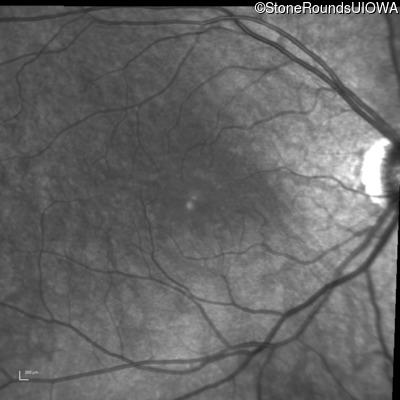

Infrared Fundus Photograph - Right - 20/40 +1

Exemplar